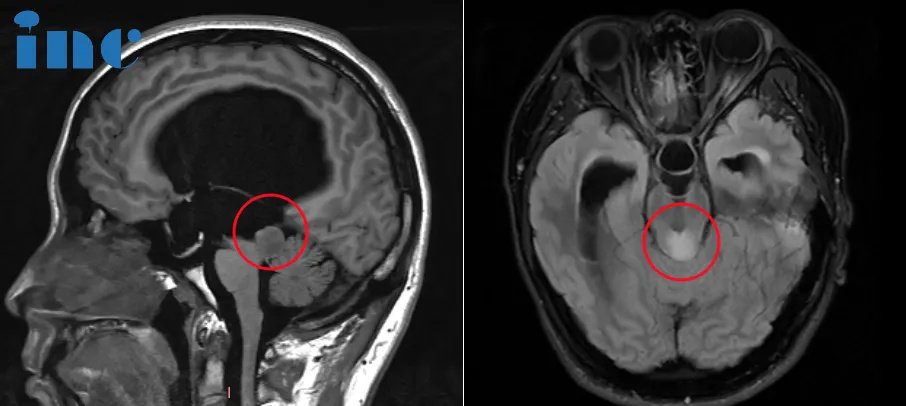

术前MRI影像

简单来说,四叠体即中脑顶盖,脑干顶盖包含上丘、下丘,是视觉、听觉反射中枢。脑干顶盖部易发胶质瘤,包括毛细胞型星形细胞瘤、星形细胞瘤、少突胶质细胞瘤、室管膜瘤,其中毛细胞型星形细胞瘤全切后,中位生存期可达40年。

脑干顶盖毗邻多个重要脑组织,包括中脑导水管、松果体、小脑、丘脑等。肿瘤生长压迫脑组织或手术术中稍有不慎就会造成眼球运动障碍、斜视、复视,听力下降、走路不稳等严重后果……